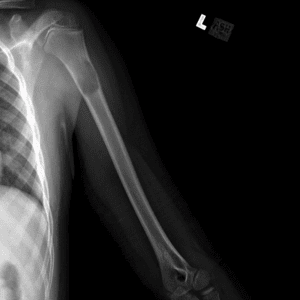

Pediatric Radiographs